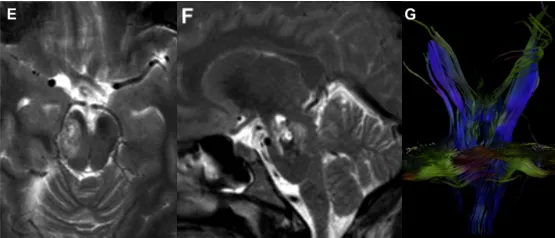

31岁孕妇,孕11周时因左侧偏瘫、吞咽困难、左侧面瘫、持续疲倦感和头痛到巴教授所在医院就诊。影像检查发现右侧脑桥中脑交界处存在病变,伴有急性出血,且周围皮质延髓束和皮质脊髓束纤维已发生移位。

起初这名孕妇选择保守观察,但仅仅过了7天,症状就明显加重。巴教授及团队经过审慎评估后,决定在孕期实施手术。为确保孕妇和胎儿的安全,术前对胎儿进行了超声检查,术中放置了腰椎引流管引流脑脊液,并在神经电生理监测和神经导航的全程护航下,实现了海绵状血管瘤的大体全切。术后复查胎儿超声,结果显示宝宝状况良好。